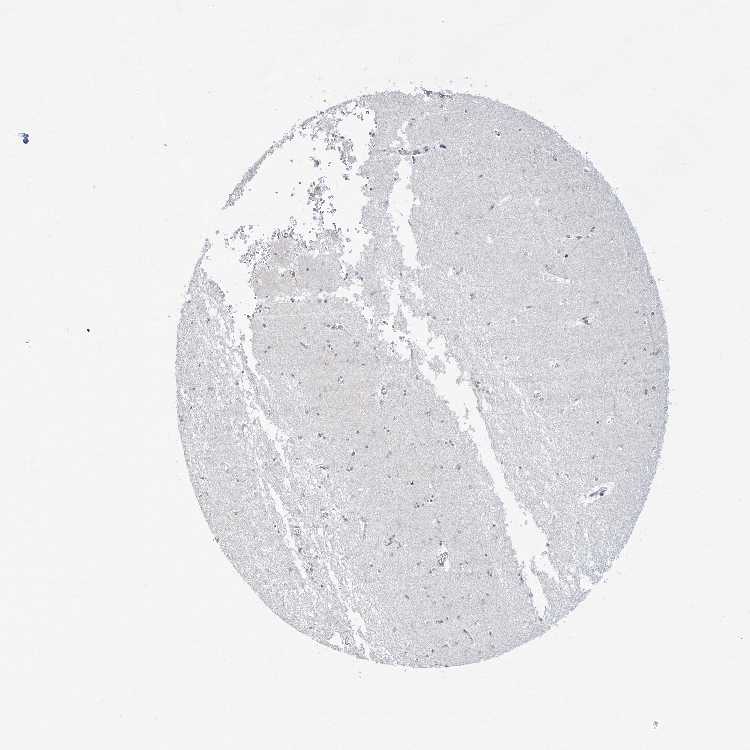

HIPPOCAMPUS - Antibody stainingi

Antibody staining in the annotated cell types in the current human tissue is reported as not detected, low, medium, or high, based on conventional immunohistochemistry profiling in selected tissues. This score is based on the combination of the staining intensity and fraction of stained cells.

Each image is clickable and will lead to virtual microscopy that enables deeper exploration of all samples and also displays staining intensity scores, fraction scores and subcellular localization as well as patient and tissue information for each sample.

Antibody HPA046387Antibody CAB037214Antibody CAB037285

Glial cells Not detectedLowMedium

Neuronal cells MediumLowNot detected